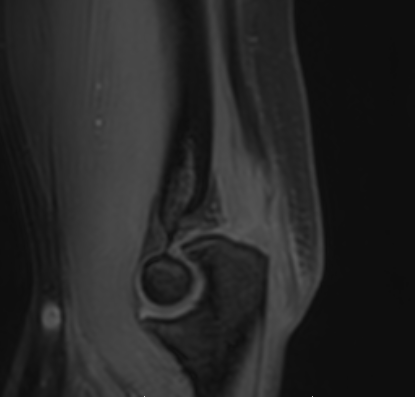

MRI